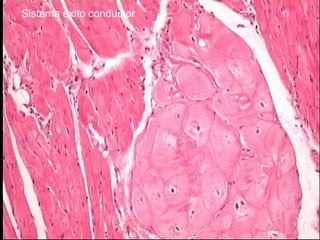

Sistema éxito-conductor

Sistema de conducción de los impulsos formado por células musculares

cardíacas modificadas y especializadas para generar y conducir impulsos

a través del corazón.

Nódulo sinoatrial: -marcapaso situado cerca de la desembocadura de la

vena cava superior en el atrio derecho.

-Células experimentan despolarización rítmica

espontánea que genera impulsos que se desplazan a

través del miocardio y activan las células

musculares normales.

-Envuelto en tejido conectivo e inervado por el

Sistema Nervioso Autónomo.

El simpático aumenta la frecuencia del latido

cardíaco. El parasimpático la reduce.

Sistema éxito conductor

• Constituido por fibras musculares estriadas

modificadas para que su velocidad de descarga

sea mas rápida que el resto del miocardio.

• Contiene mayor cantidad de glucógeno y

sarcoplasma lo que permite que su frecuencia

de descarga frente a las otras fibras

miocárdicas sea mas rápida.